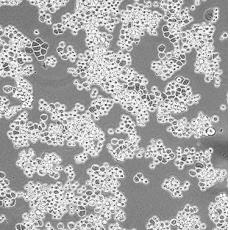

產(chǎn)品名稱 MDA-MB-453

中文名稱 人乳腺癌細胞

組織來源 乳腺腺癌;胸腔積液轉移;女性

形態(tài)特征 epithelial

細胞描述 該細胞系由CailleauR在1976年從一名48歲的患有轉移性乳腺癌的白人女性的心包滲出液中分離建立的。該細胞表達FGF的受體。